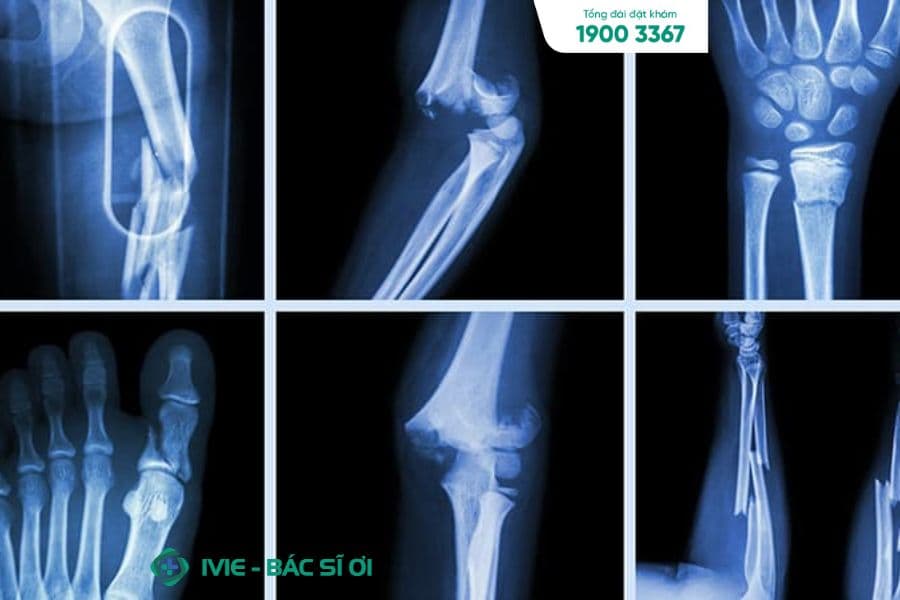

Chụp X-Quang

Chụp X-quang là phương pháp đơn giản và phổ biến nhất trong việc phát hiện ung thư xương. Quá trình này giúp bác sĩ quan sát cấu trúc của xương và phát hiện những bất thường như vết nứt, vết loang hay u cục.